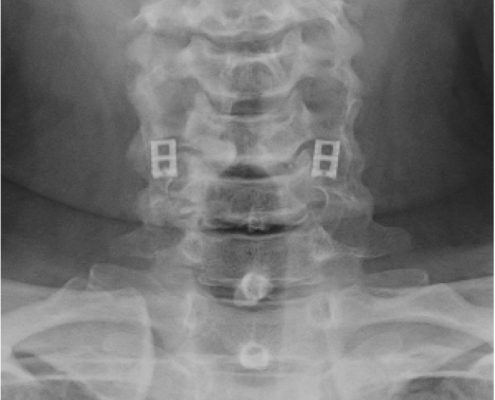

El sistema DTRAX® se compone de 2 cuñas de titanio que se introducen entre las facetas articulares cervicales para conseguir un aumento del espacio foraminal produciendo así la descompresión de la raíz o raíces nerviosas comprimidas a través de la distracción facetaria a la vez que produce una fijación estable de la articulación en el nivel implantado favoreciendo la fusión. Todo ello se realiza mediante un abordaje mínimamente invasivo gracias a un instrumental especialmente diseñado para ello.

DTRAX® está indicado para su uso en pacientes esqueléticamente maduros con patología degenerativa discal de la columna cervical (C3 a C7) con acompañamiento de radiculopatía y/o dolor facetario. La distracción facetaria que produce el DTRAX® hace que el espacio foraminal aumente aproximadamente en un 20% además de producir una estabilización de la articulación mayor en movimientos de rotación axial y movimientos laterales e igual en flexo- extensión si lo comparamos con la estabilización que produce una caja y una placa colocada mediante un abordaje anterior tradicional.